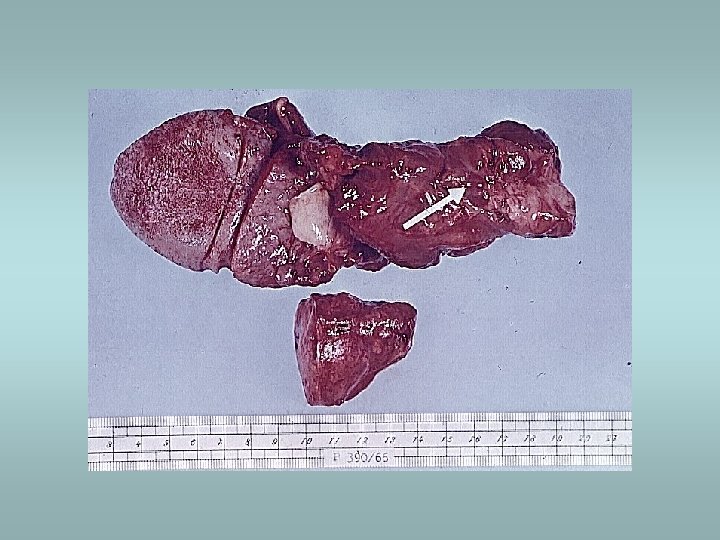

Primary acute adrenocortical insufficiency ü Rapid withdrawal of steroids ü Massive destruction of steroids – Waterhouse. Friderichsen syndrome: • • • During septic meningococcal infection Massive hemorrhage Hypotension Shock DIC

Addison’s disease (chronic adrenocortical insufficiency) ü ü Autoimunne Infection (TBC, fungi, etc. ) Metastatic cancer (lung, stomach, etc. ) Clinically: • • Anorexia Weakness Cutaneous hyperpigmentation ACTH elevation (in primary insufficiency) Secondary insufficiency ü decreased production of ACTH, absence of hyperpigmentation, normal aldosterone levels